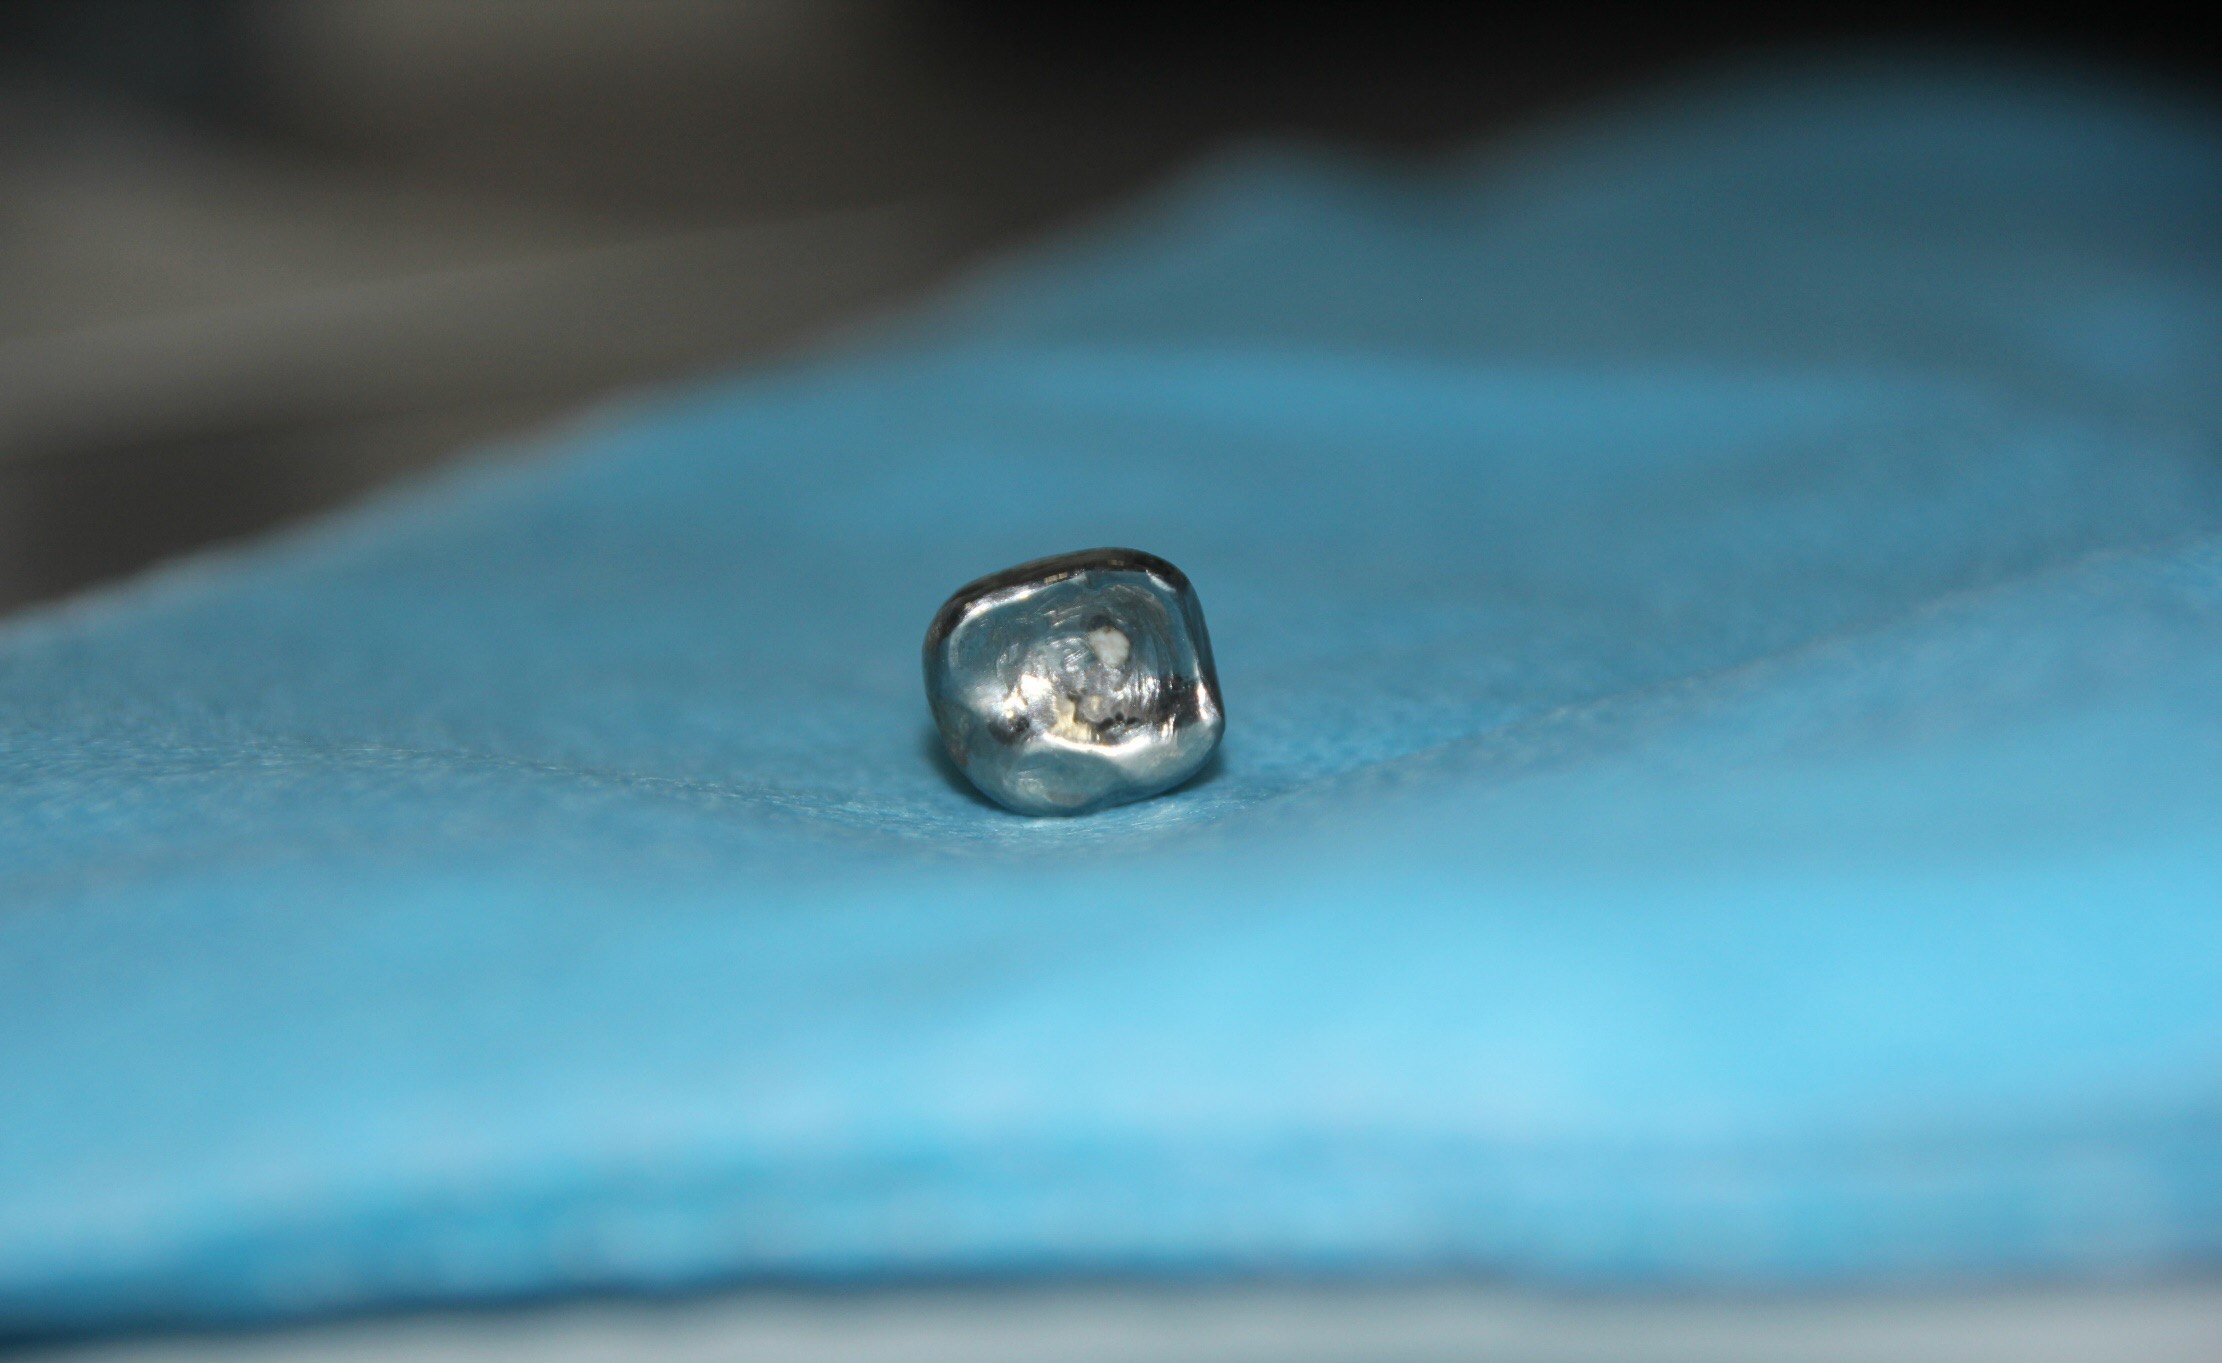

图4: 患牙拔除后,见烤瓷冠完好。

图5 图6 图7 : 洗净拔除的患牙,可见牙冠及烤瓷牙完好,牙根从颈部折裂

图4: 洗净拔除的患牙,可见牙套完好,牙根从颈部折裂

图5: 洗净拔除的患牙,可见牙套完好,牙根牙颈部结石较多。